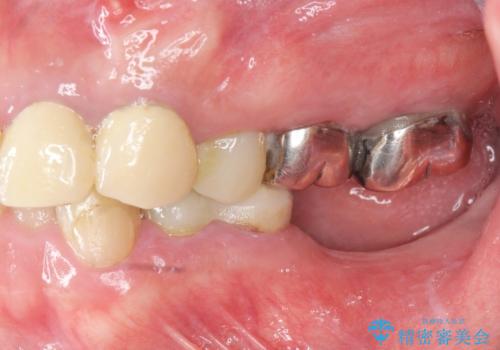

- 「少しずつ色々な箇所が悪くなり、歯医者に通い続けている。全ての歯を長持ちするような状態にできるような治療を受けたい。」、と全顎・総合的な治療を希望され来院されました。

根管治療・矯正治療・歯周外科・セラミック補綴を含む様々な治療オプションを駆使し、長期間良好な状態に保てるような治療計画を立案します。

矯正治療を絡めた総合的な治療をお行なったことで、理想的な咬合関係を確立し安定した噛み合わせで仕上げることができました。

また歯周外科を行うことで歯ぐきの腫れを改善し、清掃性を高めています。